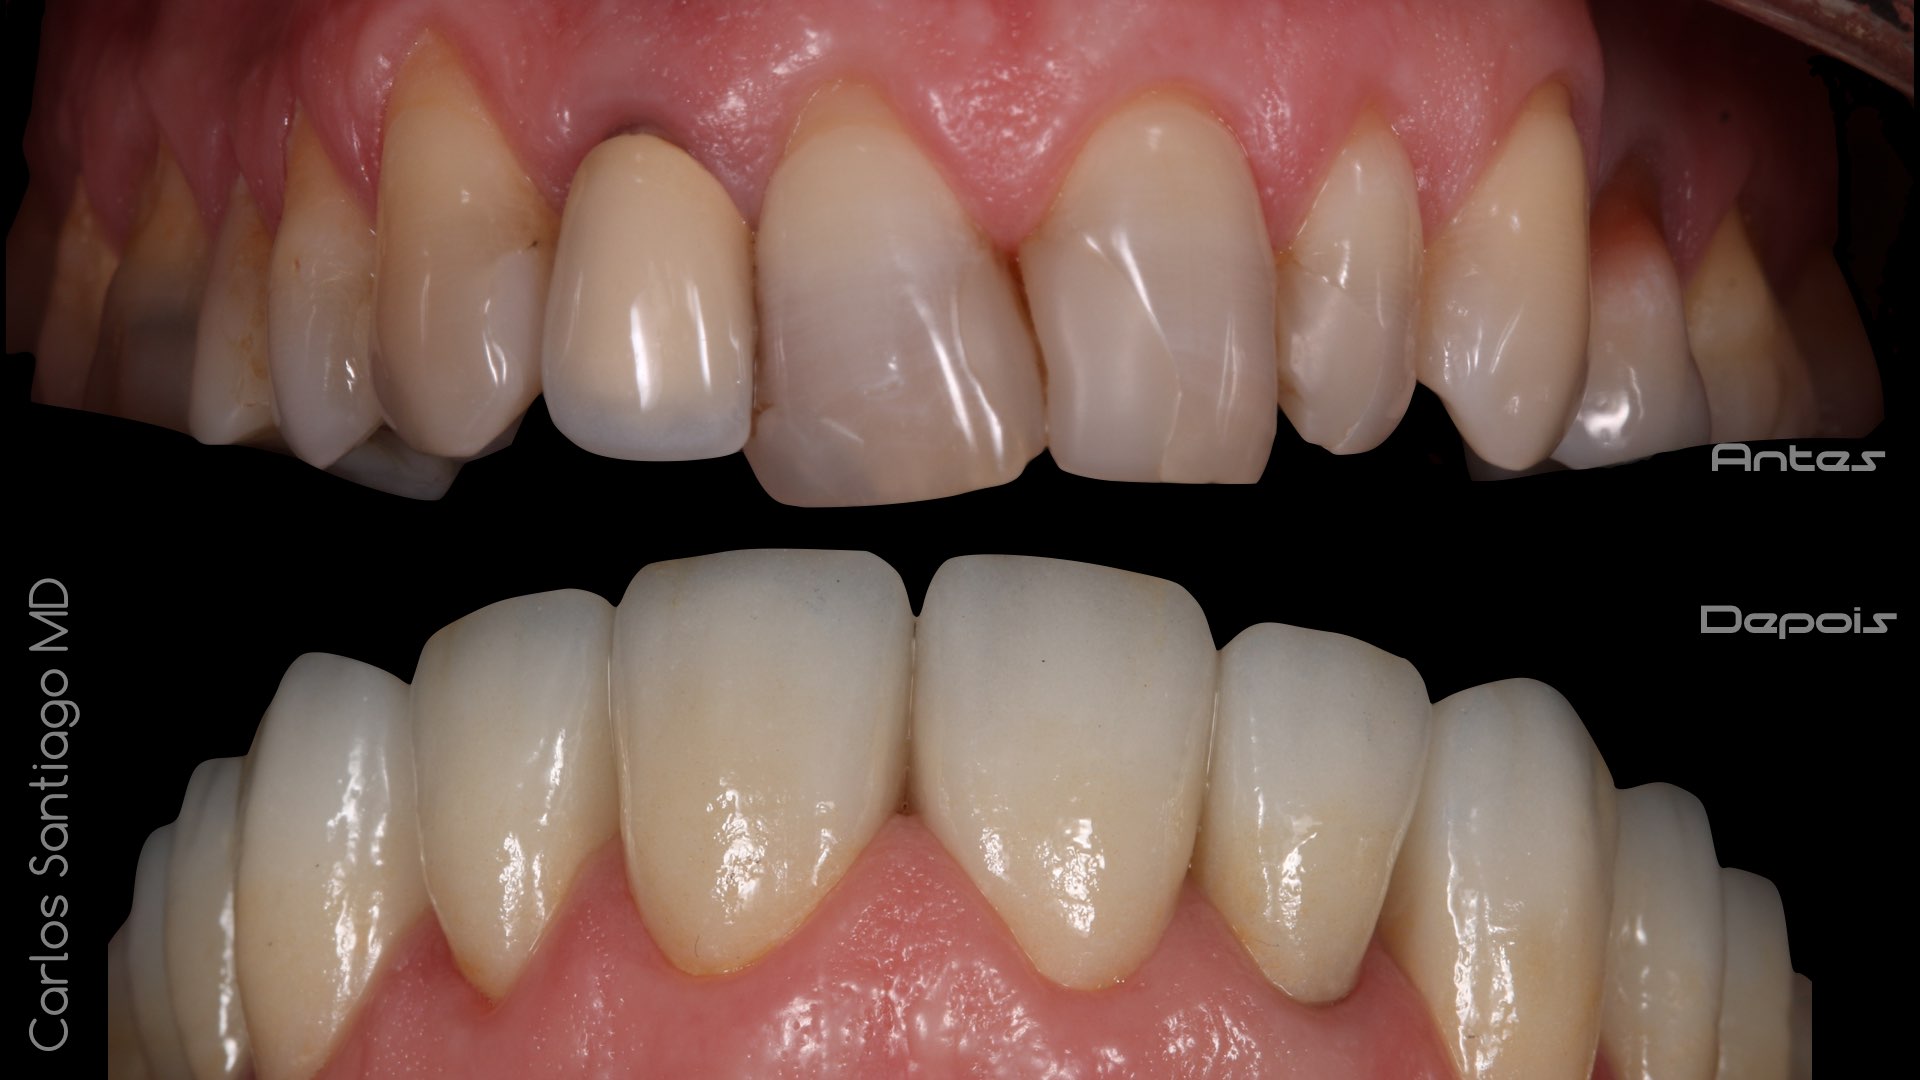

As Facetas Cerâmicas (lentes de contacto dentárias ou laminados), permitem corrigir da maneira mais estética e conservadora possível, problemas de forma e tamanho, côr e posição dos dentes, bem como substituir restaurações antigas e inestéticas.

São aderidas químicamente ao esmalte dentário de uma forma permanente, com o objectivo de melhorar a estética dos nossos pacientes.